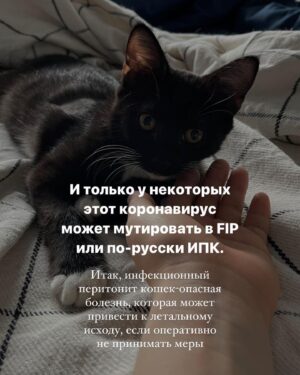

Caption : Про наших «блох», их болезнь и про классы от нас с @baturo_ Друзья, мы в конце января с Андреем взяли 3х котят из приюта. Прелестные, ласковые создания. К сожалению, двое из них заболели FIP (об этом рассказывала неделю назад, можно прочесть в карусели или в актуальном) Мы с Андреем уже очень сильно их любим, сдаваться не намерены. Четко и уверенно настроены на лучшее. Поэтому мы организовываем классы в Санкт-Петербурге 22 апреля‼️, все средства от которых пойдут на лечение наших блох, Нео и Абу. ⚫️22 апреля 15.00-17.00- Андрей Батуро (изоляция, виды) 17.00-19.00- Баина (партерная техника, основы безопасности в партере, грамотное распределение веса) ⚫️Стоимость: 1 класс-1500 руб 2 класса-2500 руб Место проведения: Jonathan, измайловский проспект, 2, зал 14 (вход со стороны измайловского проспекта) Код от домофона Внизу #1962 Наверху 2703# Проведите время с пользой для себя и помогите поправить здоровье двум маленьким котятам) Для записи пишите в директ) Мы очень будем рады видеть всех, а также просим максимально помочь с распространением этого поста, чтобы больше человек могли увидеть его)) P.S пользуясь случаем, хочу поблагодарить всех неравнодушных, кто просто захотел помочь монеткой🙏🏻🙏🏻 Это до слез ценно!Likes : 1330

Caption : Про наших «блох», их болезнь и про классы от нас с @baturo_ Друзья, мы в конце января с Андреем взяли 3х котят из приюта. Прелестные, ласковые создания. К сожалению, двое из них заболели FIP (об этом рассказывала неделю назад, можно прочесть в карусели или в актуальном) Мы с Андреем уже очень сильно их любим, сдаваться не намерены. Четко и уверенно настроены на лучшее. Поэтому мы организовываем классы в Санкт-Петербурге 22 апреля‼️, все средства от которых пойдут на лечение наших блох, Нео и Абу. ⚫️22 апреля 15.00-17.00- Андрей Батуро (изоляция, виды) 17.00-19.00- Баина (партерная техника, основы безопасности в партере, грамотное распределение веса) ⚫️Стоимость: 1 класс-1500 руб 2 класса-2500 руб Место проведения: Jonathan, измайловский проспект, 2, зал 14 (вход со стороны измайловского проспекта) Код от домофона Внизу #1962 Наверху 2703# Проведите время с пользой для себя и помогите поправить здоровье двум маленьким котятам) Для записи пишите в директ) Мы очень будем рады видеть всех, а также просим максимально помочь с распространением этого поста, чтобы больше человек могли увидеть его)) P.S пользуясь случаем, хочу поблагодарить всех неравнодушных, кто просто захотел помочь монеткой🙏🏻🙏🏻 Это до слез ценно!Likes : 1330

Caption : Про наших «блох», их болезнь и про классы от нас с @baturo_ Друзья, мы в конце января с Андреем взяли 3х котят из приюта. Прелестные, ласковые создания. К сожалению, двое из них заболели FIP (об этом рассказывала неделю назад, можно прочесть в карусели или в актуальном) Мы с Андреем уже очень сильно их любим, сдаваться не намерены. Четко и уверенно настроены на лучшее. Поэтому мы организовываем классы в Санкт-Петербурге 22 апреля‼️, все средства от которых пойдут на лечение наших блох, Нео и Абу. ⚫️22 апреля 15.00-17.00- Андрей Батуро (изоляция, виды) 17.00-19.00- Баина (партерная техника, основы безопасности в партере, грамотное распределение веса) ⚫️Стоимость: 1 класс-1500 руб 2 класса-2500 руб Место проведения: Jonathan, измайловский проспект, 2, зал 14 (вход со стороны измайловского проспекта) Код от домофона Внизу #1962 Наверху 2703# Проведите время с пользой для себя и помогите поправить здоровье двум маленьким котятам) Для записи пишите в директ) Мы очень будем рады видеть всех, а также просим максимально помочь с распространением этого поста, чтобы больше человек могли увидеть его)) P.S пользуясь случаем, хочу поблагодарить всех неравнодушных, кто просто захотел помочь монеткой🙏🏻🙏🏻 Это до слез ценно!Likes : 1330

Caption : Про наших «блох», их болезнь и про классы от нас с @baturo_ Друзья, мы в конце января с Андреем взяли 3х котят из приюта. Прелестные, ласковые создания. К сожалению, двое из них заболели FIP (об этом рассказывала неделю назад, можно прочесть в карусели или в актуальном) Мы с Андреем уже очень сильно их любим, сдаваться не намерены. Четко и уверенно настроены на лучшее. Поэтому мы организовываем классы в Санкт-Петербурге 22 апреля‼️, все средства от которых пойдут на лечение наших блох, Нео и Абу. ⚫️22 апреля 15.00-17.00- Андрей Батуро (изоляция, виды) 17.00-19.00- Баина (партерная техника, основы безопасности в партере, грамотное распределение веса) ⚫️Стоимость: 1 класс-1500 руб 2 класса-2500 руб Место проведения: Jonathan, измайловский проспект, 2, зал 14 (вход со стороны измайловского проспекта) Код от домофона Внизу #1962 Наверху 2703# Проведите время с пользой для себя и помогите поправить здоровье двум маленьким котятам) Для записи пишите в директ) Мы очень будем рады видеть всех, а также просим максимально помочь с распространением этого поста, чтобы больше человек могли увидеть его)) P.S пользуясь случаем, хочу поблагодарить всех неравнодушных, кто просто захотел помочь монеткой🙏🏻🙏🏻 Это до слез ценно!Likes : 1330

Caption : Про наших «блох», их болезнь и про классы от нас с @baturo_ Друзья, мы в конце января с Андреем взяли 3х котят из приюта. Прелестные, ласковые создания. К сожалению, двое из них заболели FIP (об этом рассказывала неделю назад, можно прочесть в карусели или в актуальном) Мы с Андреем уже очень сильно их любим, сдаваться не намерены. Четко и уверенно настроены на лучшее. Поэтому мы организовываем классы в Санкт-Петербурге 22 апреля‼️, все средства от которых пойдут на лечение наших блох, Нео и Абу. ⚫️22 апреля 15.00-17.00- Андрей Батуро (изоляция, виды) 17.00-19.00- Баина (партерная техника, основы безопасности в партере, грамотное распределение веса) ⚫️Стоимость: 1 класс-1500 руб 2 класса-2500 руб Место проведения: Jonathan, измайловский проспект, 2, зал 14 (вход со стороны измайловского проспекта) Код от домофона Внизу #1962 Наверху 2703# Проведите время с пользой для себя и помогите поправить здоровье двум маленьким котятам) Для записи пишите в директ) Мы очень будем рады видеть всех, а также просим максимально помочь с распространением этого поста, чтобы больше человек могли увидеть его)) P.S пользуясь случаем, хочу поблагодарить всех неравнодушных, кто просто захотел помочь монеткой🙏🏻🙏🏻 Это до слез ценно!Likes : 1330

Caption : Про наших «блох», их болезнь и про классы от нас с @baturo_ Друзья, мы в конце января с Андреем взяли 3х котят из приюта. Прелестные, ласковые создания. К сожалению, двое из них заболели FIP (об этом рассказывала неделю назад, можно прочесть в карусели или в актуальном) Мы с Андреем уже очень сильно их любим, сдаваться не намерены. Четко и уверенно настроены на лучшее. Поэтому мы организовываем классы в Санкт-Петербурге 22 апреля‼️, все средства от которых пойдут на лечение наших блох, Нео и Абу. ⚫️22 апреля 15.00-17.00- Андрей Батуро (изоляция, виды) 17.00-19.00- Баина (партерная техника, основы безопасности в партере, грамотное распределение веса) ⚫️Стоимость: 1 класс-1500 руб 2 класса-2500 руб Место проведения: Jonathan, измайловский проспект, 2, зал 14 (вход со стороны измайловского проспекта) Код от домофона Внизу #1962 Наверху 2703# Проведите время с пользой для себя и помогите поправить здоровье двум маленьким котятам) Для записи пишите в директ) Мы очень будем рады видеть всех, а также просим максимально помочь с распространением этого поста, чтобы больше человек могли увидеть его)) P.S пользуясь случаем, хочу поблагодарить всех неравнодушных, кто просто захотел помочь монеткой🙏🏻🙏🏻 Это до слез ценно!Likes : 1330

Caption : Про наших «блох», их болезнь и про классы от нас с @baturo_ Друзья, мы в конце января с Андреем взяли 3х котят из приюта. Прелестные, ласковые создания. К сожалению, двое из них заболели FIP (об этом рассказывала неделю назад, можно прочесть в карусели или в актуальном) Мы с Андреем уже очень сильно их любим, сдаваться не намерены. Четко и уверенно настроены на лучшее. Поэтому мы организовываем классы в Санкт-Петербурге 22 апреля‼️, все средства от которых пойдут на лечение наших блох, Нео и Абу. ⚫️22 апреля 15.00-17.00- Андрей Батуро (изоляция, виды) 17.00-19.00- Баина (партерная техника, основы безопасности в партере, грамотное распределение веса) ⚫️Стоимость: 1 класс-1500 руб 2 класса-2500 руб Место проведения: Jonathan, измайловский проспект, 2, зал 14 (вход со стороны измайловского проспекта) Код от домофона Внизу #1962 Наверху 2703# Проведите время с пользой для себя и помогите поправить здоровье двум маленьким котятам) Для записи пишите в директ) Мы очень будем рады видеть всех, а также просим максимально помочь с распространением этого поста, чтобы больше человек могли увидеть его)) P.S пользуясь случаем, хочу поблагодарить всех неравнодушных, кто просто захотел помочь монеткой🙏🏻🙏🏻 Это до слез ценно!Likes : 1330

Caption : Про наших «блох», их болезнь и про классы от нас с @baturo_ Друзья, мы в конце января с Андреем взяли 3х котят из приюта. Прелестные, ласковые создания. К сожалению, двое из них заболели FIP (об этом рассказывала неделю назад, можно прочесть в карусели или в актуальном) Мы с Андреем уже очень сильно их любим, сдаваться не намерены. Четко и уверенно настроены на лучшее. Поэтому мы организовываем классы в Санкт-Петербурге 22 апреля‼️, все средства от которых пойдут на лечение наших блох, Нео и Абу. ⚫️22 апреля 15.00-17.00- Андрей Батуро (изоляция, виды) 17.00-19.00- Баина (партерная техника, основы безопасности в партере, грамотное распределение веса) ⚫️Стоимость: 1 класс-1500 руб 2 класса-2500 руб Место проведения: Jonathan, измайловский проспект, 2, зал 14 (вход со стороны измайловского проспекта) Код от домофона Внизу #1962 Наверху 2703# Проведите время с пользой для себя и помогите поправить здоровье двум маленьким котятам) Для записи пишите в директ) Мы очень будем рады видеть всех, а также просим максимально помочь с распространением этого поста, чтобы больше человек могли увидеть его)) P.S пользуясь случаем, хочу поблагодарить всех неравнодушных, кто просто захотел помочь монеткой🙏🏻🙏🏻 Это до слез ценно!Likes : 1330

Caption : Про наших «блох», их болезнь и про классы от нас с @baturo_ Друзья, мы в конце января с Андреем взяли 3х котят из приюта. Прелестные, ласковые создания. К сожалению, двое из них заболели FIP (об этом рассказывала неделю назад, можно прочесть в карусели или в актуальном) Мы с Андреем уже очень сильно их любим, сдаваться не намерены. Четко и уверенно настроены на лучшее. Поэтому мы организовываем классы в Санкт-Петербурге 22 апреля‼️, все средства от которых пойдут на лечение наших блох, Нео и Абу. ⚫️22 апреля 15.00-17.00- Андрей Батуро (изоляция, виды) 17.00-19.00- Баина (партерная техника, основы безопасности в партере, грамотное распределение веса) ⚫️Стоимость: 1 класс-1500 руб 2 класса-2500 руб Место проведения: Jonathan, измайловский проспект, 2, зал 14 (вход со стороны измайловского проспекта) Код от домофона Внизу #1962 Наверху 2703# Проведите время с пользой для себя и помогите поправить здоровье двум маленьким котятам) Для записи пишите в директ) Мы очень будем рады видеть всех, а также просим максимально помочь с распространением этого поста, чтобы больше человек могли увидеть его)) P.S пользуясь случаем, хочу поблагодарить всех неравнодушных, кто просто захотел помочь монеткой🙏🏻🙏🏻 Это до слез ценно!Likes : 1330

Caption : Про наших «блох», их болезнь и про классы от нас с @baturo_ Друзья, мы в конце января с Андреем взяли 3х котят из приюта. Прелестные, ласковые создания. К сожалению, двое из них заболели FIP (об этом рассказывала неделю назад, можно прочесть в карусели или в актуальном) Мы с Андреем уже очень сильно их любим, сдаваться не намерены. Четко и уверенно настроены на лучшее. Поэтому мы организовываем классы в Санкт-Петербурге 22 апреля‼️, все средства от которых пойдут на лечение наших блох, Нео и Абу. ⚫️22 апреля 15.00-17.00- Андрей Батуро (изоляция, виды) 17.00-19.00- Баина (партерная техника, основы безопасности в партере, грамотное распределение веса) ⚫️Стоимость: 1 класс-1500 руб 2 класса-2500 руб Место проведения: Jonathan, измайловский проспект, 2, зал 14 (вход со стороны измайловского проспекта) Код от домофона Внизу #1962 Наверху 2703# Проведите время с пользой для себя и помогите поправить здоровье двум маленьким котятам) Для записи пишите в директ) Мы очень будем рады видеть всех, а также просим максимально помочь с распространением этого поста, чтобы больше человек могли увидеть его)) P.S пользуясь случаем, хочу поблагодарить всех неравнодушных, кто просто захотел помочь монеткой🙏🏻🙏🏻 Это до слез ценно!Likes : 1330